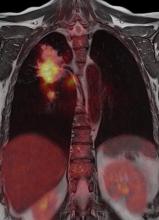

In a comparison of patients with Stage-1 non-small cell lung cancer (NSCLC) during the period 1999-2008, those in the last four years of that period who received radiation therapy had a median survival rate of 21 months, which was markedly better than the 16-month rate among similar patients in the first four years. These study results were presented by lead author Nirav S. Kapadia, M.D., chief resident, department of radiation oncology, University of Michigan Medical School, during the 2012 Chicago Multidisciplinary Symposium in Thoracic Oncology.

The introduction of hybrid technology — positron emission tomography/computed tomography (PET/CT) and single-photon emission computed tomography (SPECT)/CT -— has revolutionized the imaging world. This technology allows the combination of the exquisite anatomic details provided, for example, by CT, with the important and much needed functional, physiologic or metabolic information provided by molecular imaging.